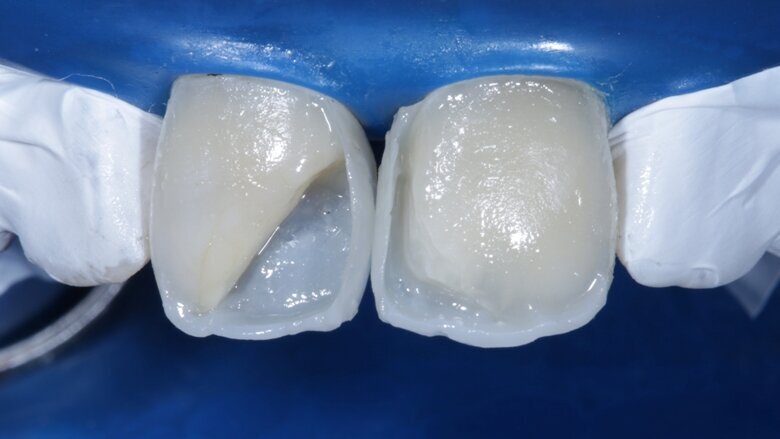

Two weeks later, the shade [ Fig 3 ] stabilized and the teeth were ready for bonding. We observed that the central incisors were still darker than the neighboring teeth. Direct composite veneers were planned with the help of a lab made wax up [ Fig 4 ] and a putty index. Bevels were placed and most of the preparation was in enamel. After the total etch protocol, 5th generation bonding agent was used. 3M Z350XT shades were used for the build up. A2 Enamel shade was used for the palatal shell [ Fig 6 ] and the proximal walls [ Fig 11 ].

Desaturation was achieved by layering a deeper darker dentin [ A3 Dentin - Fig 12 ] inside and a lighter dentin [ A2 Dentin - Fig 13 ] shade over it in the shape of three mamelons. Incisal Halo was achieved by layering an Achromatic Enamel [clear translucent] shade around the mamelons [ Fig 14 ] and the A2 dentin shade on the incisal edge [ Fig 11 ]. Final layer of A2 Enamel shade was used covering the restoration in 0.5mm thickness so as to avoid too much translucency [ Fig 15 ]. Finishing and polishing were done using the 3M Soflex discs and spirals [ Fig 17 ] as recommended by the manufacturer.

Fig 12 Dark dentin shade layered

Fig 13 light dentin shade placed above dark dentin